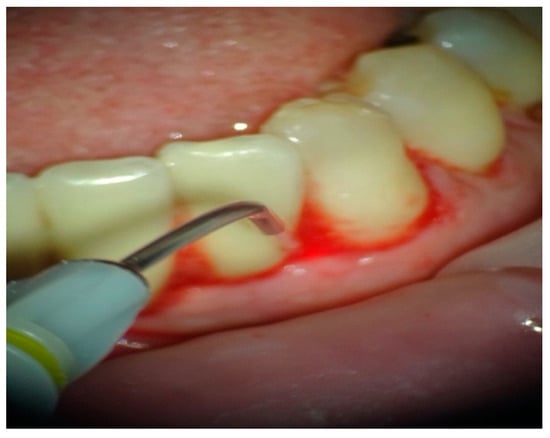

In group B, treated with the OHLLT protocol, a microbiological sampling of the periodontal pockets was made first. Then a supra and subgingival scaling with high-frequency ultrasound was made with a solution of Betadine diluted at 10% (Figure 1). An airflow session with erythritol was performed (Figure 2), and then diode laser treatment with a Sioxyl® solution was performed, irrigating the periodontal pockets with the Sioxyl® solution (Figure 3), leaving the solution for at least 2 min and irradiating with a Wiser diode laser with a peak power of 2.5 W, T-On of 20 microns, T-Off of 80 microns, average power of 0.5 W, duty cycle of 100 microns and frequency of 10 KHz (Figure 4).

Figure 4.

Treatment with a Wiser diode laser with a peak power of 2.5 W, T-On of 20 microns, T-Off of 80 microns, average power of 0.5 W, duty cycle of 100 microns and frequency of 10 KHz.